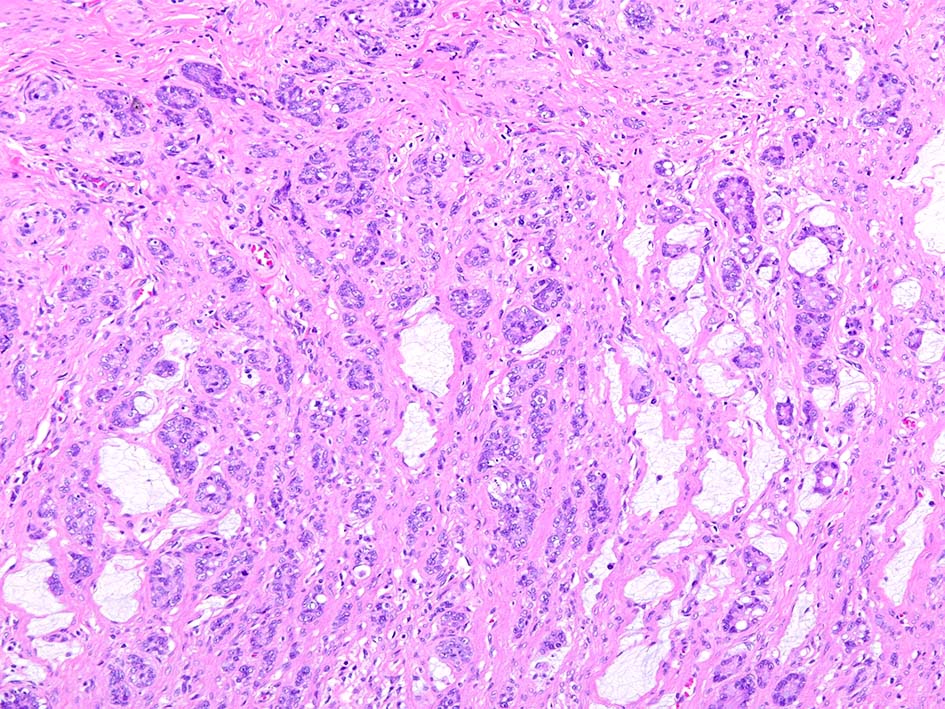

Goblet cell carcinoid tumor of the appendix

31歳 女性 X年4月下腹部痛で虫垂炎と診断され保存的治療をおこなう. 同年 7月手術を希望し腹腔鏡下虫垂切除術が施行される.

組織所見